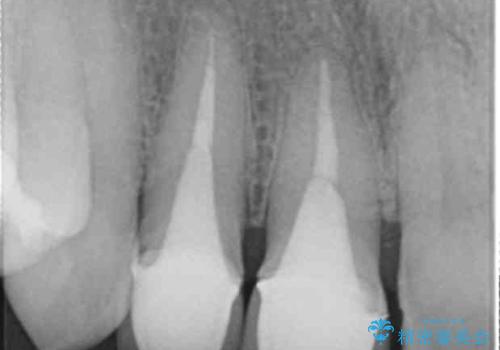

右上の前歯二本、左上の前歯1本をセラミックにし、正中の前歯を2本連結しました。

- 60.5万円(税込み) ジルコニアクラウンスペシャル 14.3万円x3 仮歯 1.1万円x3 右上1、右上2:ファイバーコア 2.2万円x2 右上1: 精密根管治療(リトリートメント) 9.9 万円x1費用は治療当時の料金となります

歯周病や楽器の影響などですき間が生じることはありますが、今回は開いてきた原因はわからないため、連結するか、ナイトガードをはめて歯ぎしりで力がかかりすぎないようにすることが大事になってきます。